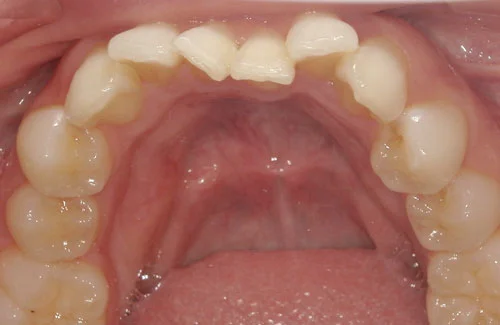

<症例7>歯がガタガタで噛み合わせが悪くお悩み

抜歯無し・マウスピースのみで矯正した症例です。

もともと歯列弓が非常に狭く、V字に近い形をしていたので噛み合わせも非常に不安定でした。

また、下顎前歯部がかなり上の方に生えていたため、下の前歯が上の前歯を突き上げてしまい出っ歯の状態になっていました。

現在では見た目はもちろん、臼歯の噛み合わせも改善しております。

奥歯の患者様も大喜びでした。

患者様と症状

主訴:歯のガタガタ、噛み合わせが悪い

性別・年齢:20代女性

問題点:叢生(重度)、V字歯列弓、ディープバイト

診断:前歯部の叢生を伴うアングルⅠ級、骨格性Ⅰ級の不正咬合

主なリスク:臼歯の移動に伴い一時的に咬合しにくくなる、歯肉退縮

症状:叢生(そうせい) 過蓋咬合(かがいこうごう)

治療内容

治療期間:1年10ヶ月

治療費用:990,000円(税込)

プラン:Full2プラン

抜歯:無し

再診治療費:無し

追加治療費:無し

保定装置費:無し

治療前後の写真